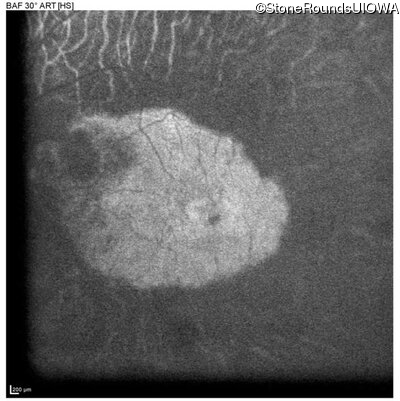

Age at visit: 60 years

This 60 year old man has had poor vision in dim light since about age 10. He lost vision in his right eye at about 16 due to toxoplasmosis. He has a mature cataract in the right eye with no view of the posterior pole. The retina in the right eye is attached by ultrasound.

AR Retinitis Pigmentosa PDE6B Pro496 del1gggC His557Tyr CAC>TAC AR